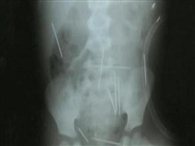

Padrasto confessa ter colocado 40 agulhas em menino na BA

Roberto Carlos Magalhães Lopes disse que teve ajuda de outras duas mulheres para colocar as agulhas na criança. O menino de 2 anos foi internado em estado grave, com agulhas espalhadas por todo o corpo.